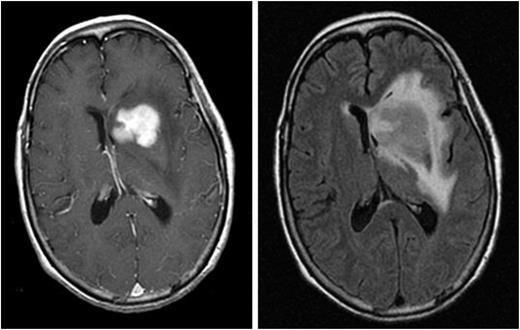

Neurocognitive symptoms are the most common presenting clinical features of PCNSL. The International PCNSL Collaborative Group (IPCG) has developed guidelines to determine extent of disease.7 A gadolinium-enhanced brain magnetic resonance imaging (MRI) scan is the most sensitive radiographic study for the detection of PCNSL (Figure 1). Most PCNSL patients present with a single brain mass. The diagnosis of PCNSL is typically established by stereotactic brain biopsy, cerebrospinal fluid (CSF) analysis, or by analysis of vitreous aspirate in patients with ocular involvement. Given the possible delay in diagnosis and treatment with the latter 2 methods, prompt stereotactic biopsy is advised in almost all cases that are surgically accessible. Corticosteroids have lymphotoxic effects and should be avoided, if possible, before stereotactic biopsy as a histopathologic diagnosis can be difficult or impossible to achieve after exposure to these drugs. Secondary CSF and ocular involvement occurs in ∼15% to 20% and 5% to 20% of PCNSL patients, respectively. Presenting symptoms of ocular involvement include eye pain, blurred vision, and floaters.8 B symptoms such as weight loss, fevers, and night sweats are infrequent in PCNSL. A thorough diagnostic evaluation is needed to establish the extent of the lymphoma and to confirm localization to the CNS. A lumbar puncture should be performed if not contraindicated, and CSF should be assessed by flow cytometry, cytology, and immunoglobulin heavy-chain gene rearrangement. Because extraneural disease must be excluded to establish a diagnosis of primary CNS lymphoma, computed tomography/positron emission tomography scans of the chest, abdomen, and pelvis, and a bone marrow biopsy and aspirate should be performed to exclude occult systemic disease. Involvement of the optic nerve, retina, or vitreous humor should be excluded with a comprehensive eye evaluation by an ophthalmologist that includes a slit-lamp examination. Blood tests should include serum lactate dehydrogenase and HIV serology.7

Magnetic resonance images from a patient with PCNSL. A T1-weighted, axial, postcontrast scan (left) demonstrates intense, homogenous enhancement of the tumor in the region of the left caudate nucleus. An axial T2/FLAIR scan at the same anatomical level (right) demonstrates hyperintense signal surrounding the tumor, reflecting vasogenic cerebral edema. (Courtesy Priscilla K. Brastianos, M.D.)